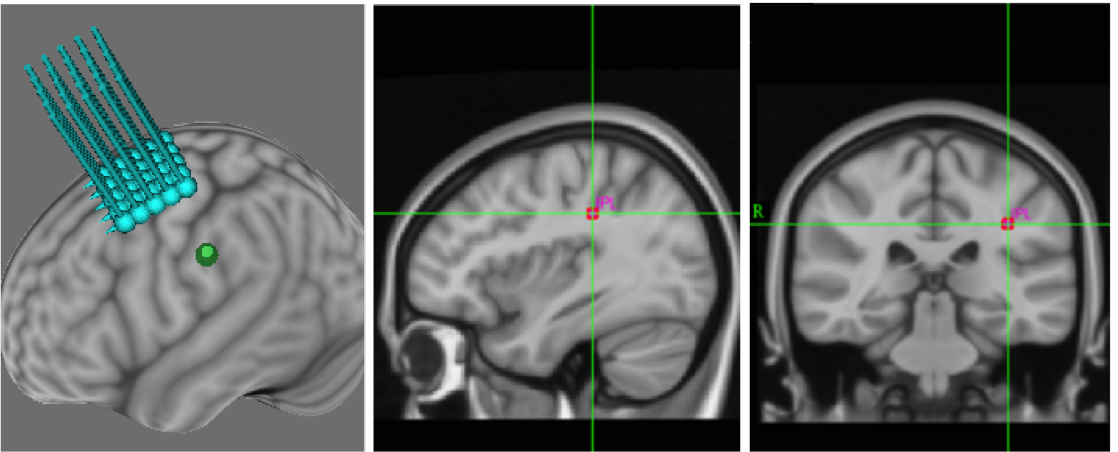

New work from the lab shows that inhibitory brain stimulation – stimulation that temporarily turns down activity in parts of the brain – can prevent learning. The work, recently accepted for publication in Experimental Brain Research, was part of lab member Sarah Kraeutner’s MSc thesis. Sarah shows that when a person uses motor imagery to learn a new task, but activity in the parietal cortex is inhibited, they’re unable to learn. The work provides good information about how learning through motor imagery occurs, as well as identifying people who might not be able to use imagery for learning.